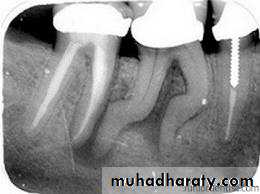

Root canal therapy such as pulpectomy, non surgical treatment of root canal system with or without periapical pathosis of pulpal origin and the obturation of these root canal systems

Obturation phase: in which the root canal is filled three dimensionally to ensure tight seal.